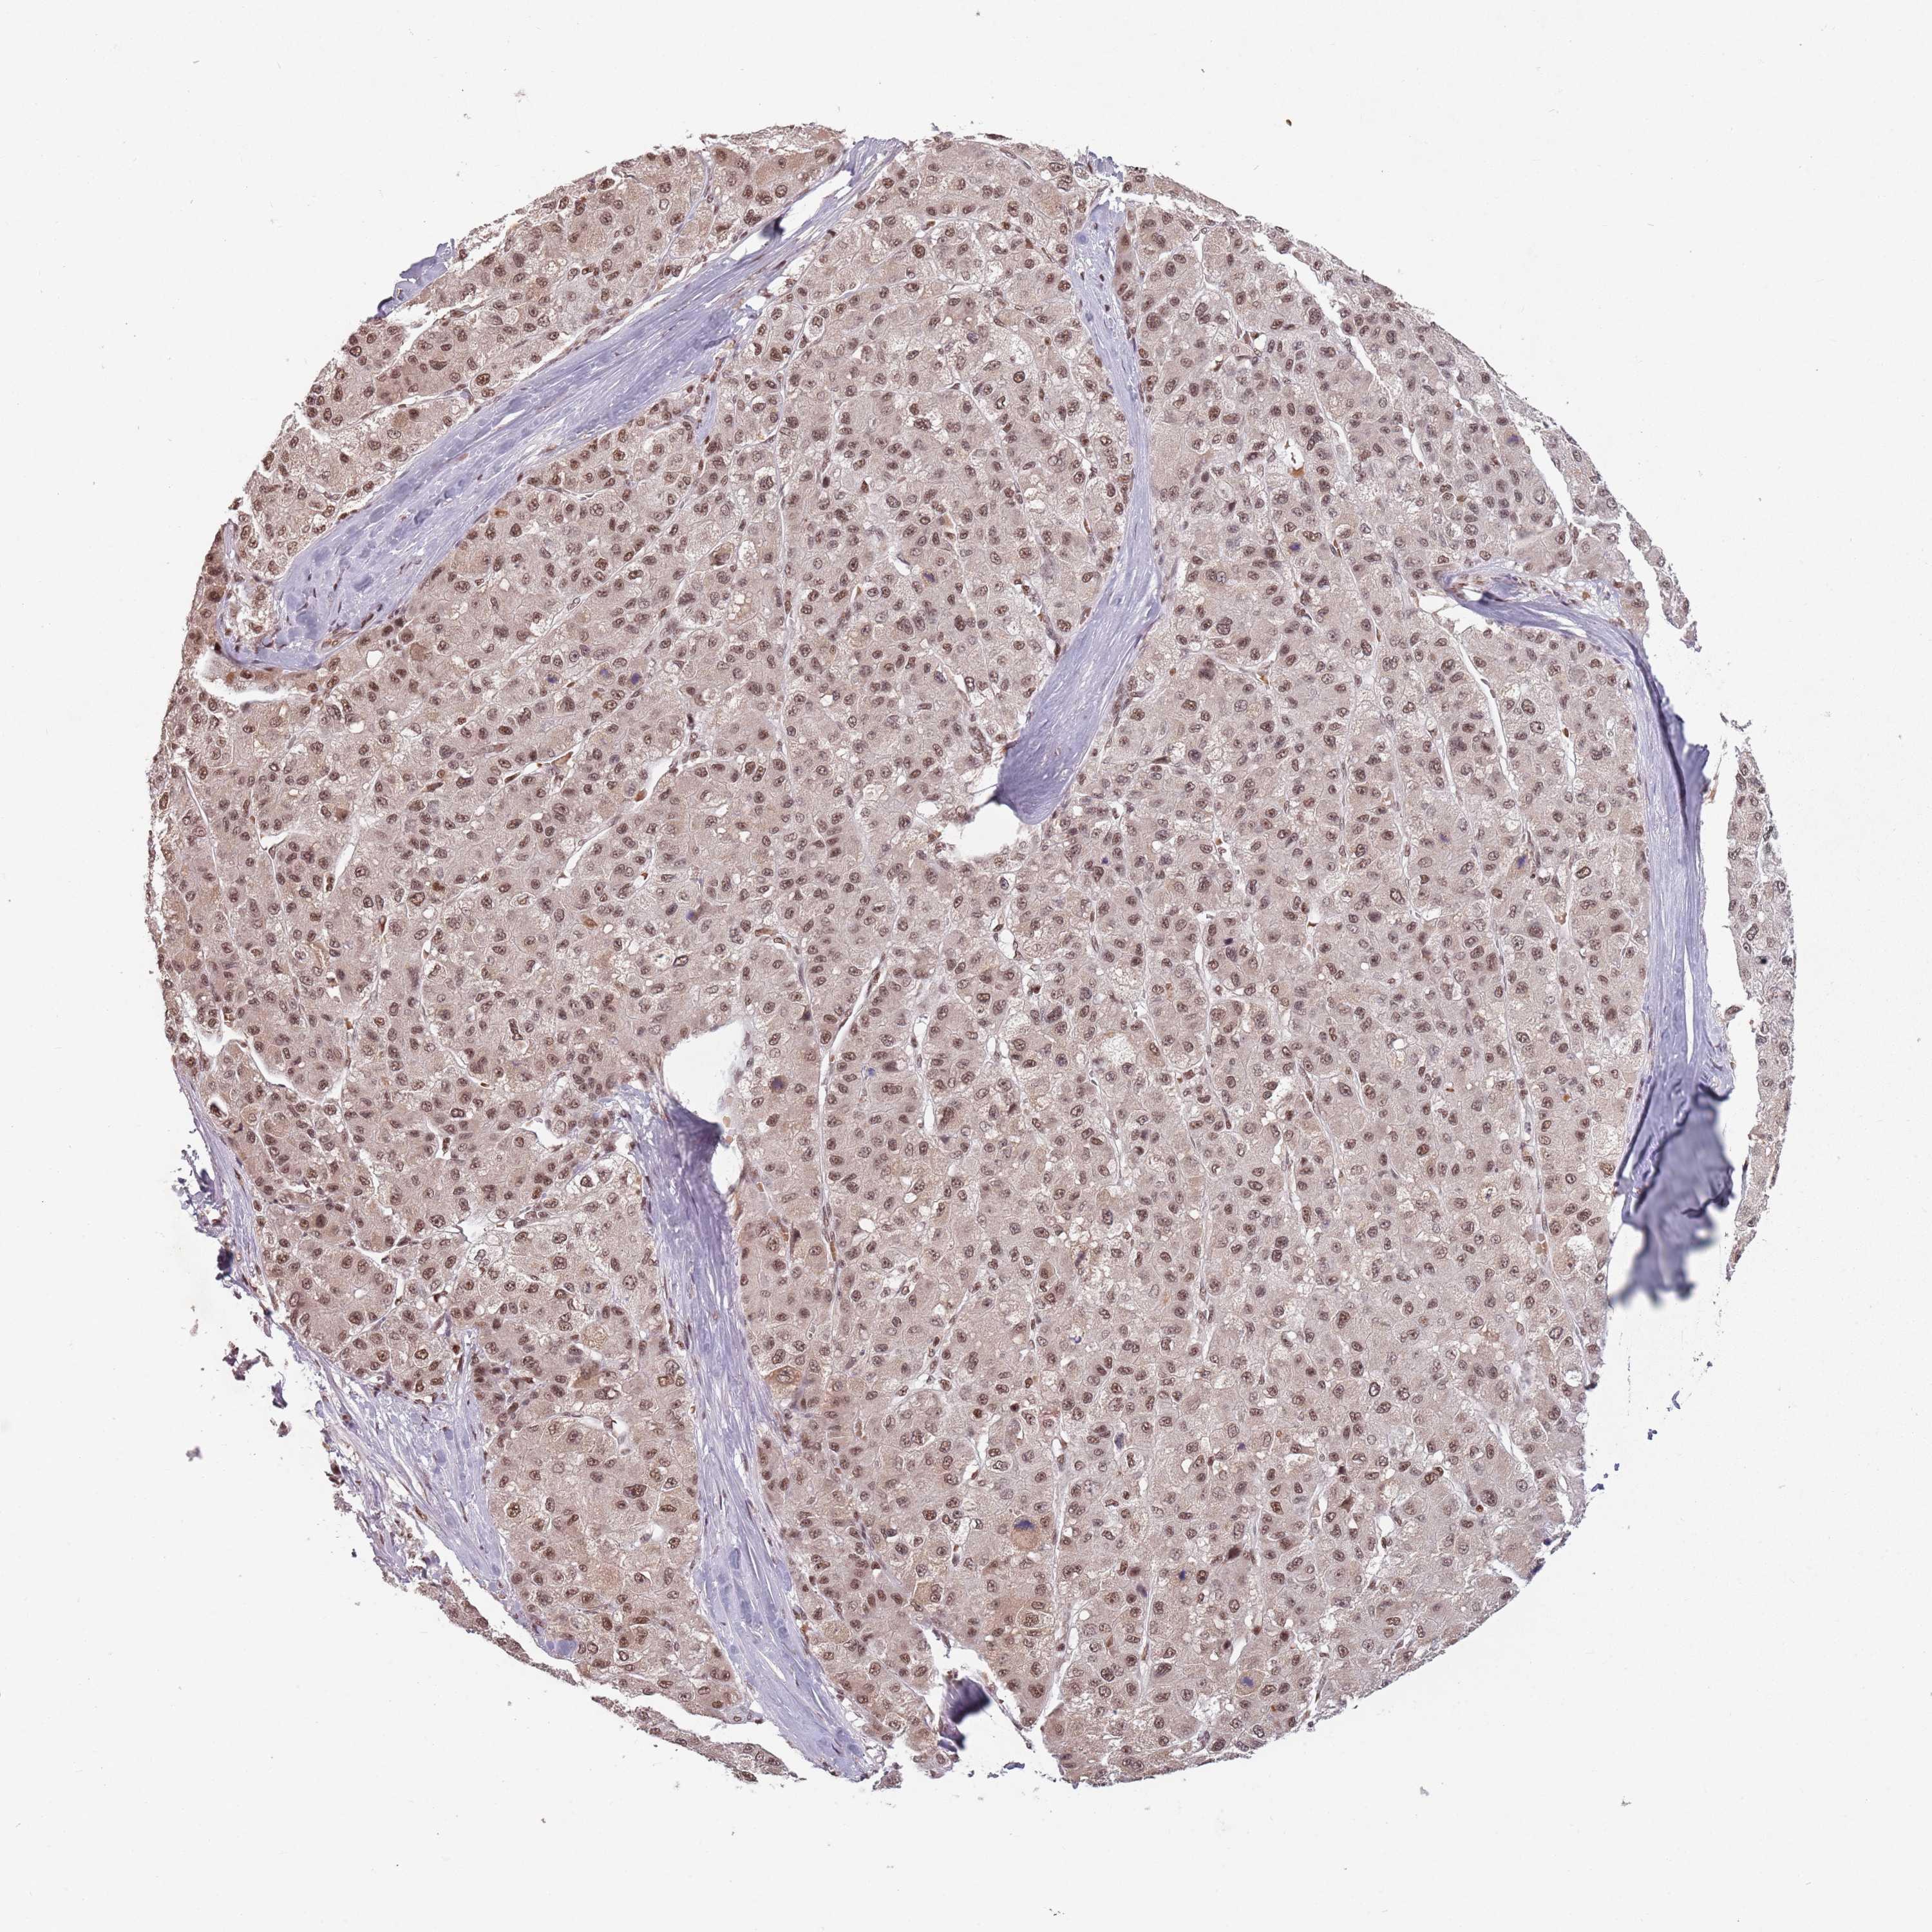

LIVER CANCER - Protein expressioni

A mouse-over function shows sample information and annotation data. Click on an image to view it in a full screen mode. Samples can be filtered based on level of antibody staining by selecting one or several of the following categories: high, medium, low and not detected. The assay and annotation is described here.

Note that samples used for immunohistochemistry by the Human Protein Atlas do not correspond to samples in the TCGA dataset.

Antibody stainingi

Antibody staining in the annotated cell types in the current human tissue is reported as not detected, low, medium, or high, based on conventional immunohistochemistry profiling in selected tissues. This score is based on the combination of the staining intensity and fraction of stained cells.

Each image is clickable and will lead to virtual microscopy that enables deeper exploration of all samples and also displays staining intensity scores, fraction scores and subcellular localization as well as patient and tissue information for each sample.

Antibody HPA042411

Antibody HPA049031

Staining

High

Medium

Low

Not detected

Intensity

Strong

Moderate

Weak

Negative

Quantity

>75%

75%-25%

<25%

None

Location

Nuclear

Cytoplasmic/membranous

Cytoplasmic/membranous,nuclear

Cholangiocarcinoma

Carcinoma, Hepatocellular, NOS